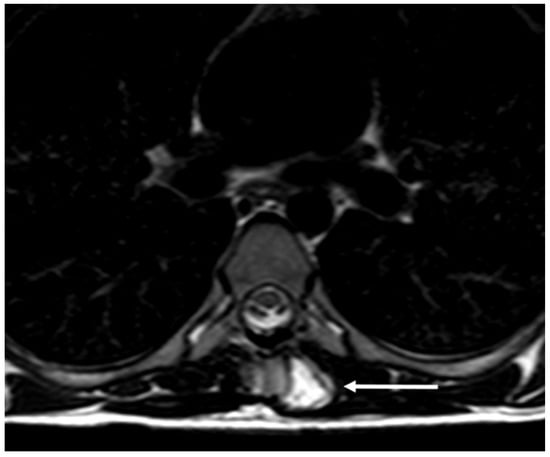

3.5. Osteochondroma

| Osteochondroma | Lesion continuity with cortex and medulla. | Cartilage cap |